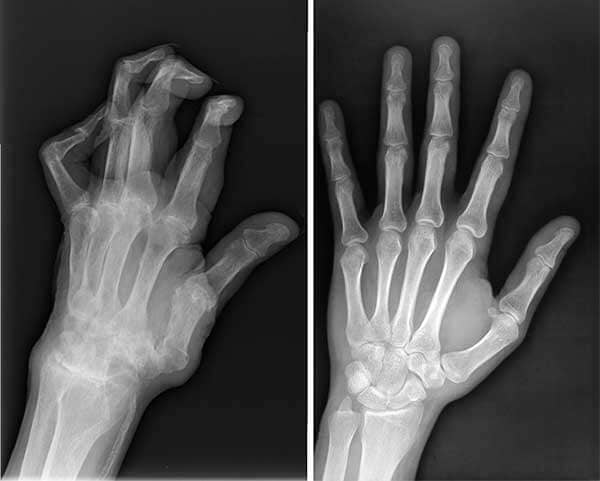

Imagen 12

Radiografías de las manos de Carlos, antes y después de Flexacil.

Imagen 13

Se nota la mejoría en la movilidad de sus dedos.